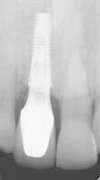

Voici la radiographie de contrôle :

Ce traitement est extrêmement fiable et permet une esthétique optimale. On peut observer lorsque la patiente sourit et en très gros plan, une parfaite ostéointégration de la prothèse.